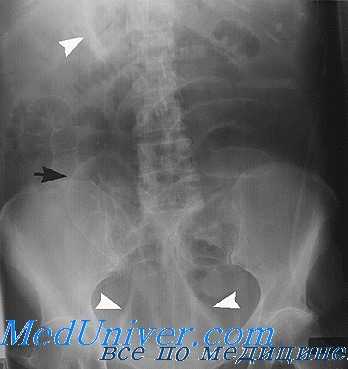

На обзорном снимке или на флюоресцирующем экране брюшная полость отображается в виде более или менее однородной средней интенсивности теневой картиной на фоне скелета данной области. Это объясняется тем, что органы брюшной полости: печень, селезенка, желудок, кишечник и т. д. имеют одинаковую плотность и рентгенологически не дифференцируются раздельно друг от друга. Но нередко на обзорном снимке бывает видна верхняя часть желудка (так как в ней содержится воздух) — в виде так называемого желудочного пузыря. Иногда бывают видны небольшие скопления газа в петлях тонкого и особенно толстого кишечника — в печеночном и селезеночном изгибах. Прямая кишка часто содержит газ и твердые каловые массы и легко поэтому иногда распознается по своей форме и положению.

Лучевые методы исследования желудка. Рентгенография желудка